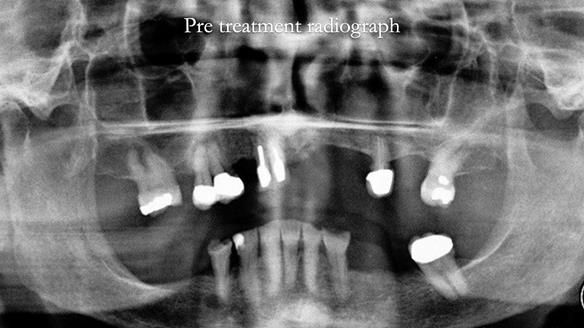

Aesthetically and functionally poor RPDs were replaced for Eileen, a 74 year old woman.

Referred to me by her general dental practitioner specifically for replacement RPDs.

Diagnoses

- Missing teeth in the upper and lower jaws

- Upper and lower metal based RPDs, poorly fitting, worn occlusal surface, reverse curve aesthetics, lacking support

- The upper right central and lateral incisors with post crowns. Healthy and functionally secure but with poor appearance, contributing to the reverse curve.

- Moderate to heavily restored dentition with deep overbite (Class 2 div II)

- Decoronate post crowns upper right lateral and central incisors to use as over denture abutment supports

- Add upper right lateral and central incisor denture teeth to existing upper RPD as temporary measure during making of new RPDs

- Composite rest seats on the lower anterior teeth and reshaping existing crown

- Composite onlay lower right first premolar – designed to support new lower RPD

- New metal based upper and lower RPDs of Scandinavian design for improved, periodontal health, function and appearance.

The clinical situation and treatment process is shown in detail below with photographs. I provided the clinical work. Rowan Garstang provided the technical work.